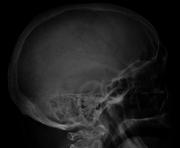

Bone pain affects almost 70% of people with multiple myeloma and is the one of the most common symptoms.[2]:653[16] Myeloma bone pain usually involves the spine and ribs, and worsens with activity. Persistent, localized pain may indicate a pathological bone fracture. Involvement of the vertebrae may lead to spinal cord compression or kyphosis. Myeloma bone disease is due to the overexpression of receptor activator for nuclear factor κ B ligand (RANKL) by bone marrow stroma. RANKL activates osteoclasts, which resorb bone. The resultant bone lesions are lytic (cause breakdown) in nature, and are best seen in plain radiographs, which may show "punched-out" resorptive lesions (including the "raindrop" appearance of the skull on radiography). The breakdown of bone also leads to the release of calcium ions into the blood, leading to hypercalcemia and its associated symptoms.

Medical imaging

The diagnostic examination of a person with suspected multiple myeloma typically includes a skeletal survey. This is a series of X-rays of the skull, axial skeleton, and proximal long bones. Myeloma activity sometimes appears as "lytic lesions" (with local disappearance of normal bone due to resorption). And on the skull X-ray as "punched-out lesions" (pepper-pot skull). Lesions may also be sclerotic, which is seen as radiodense.[52] Overall, the radiodensity of myeloma is between −30 and 120 Hounsfield units (HU).[53] Magnetic resonance imaging is more sensitive than simple X-rays in the detection of lytic lesions, and may supersede a skeletal survey, especially when vertebral disease is suspected. Occasionally, a CT scan is performed to measure the size of soft-tissue plasmacytomas. Bone scans are typically not of any additional value in the workup of people with myeloma (no new bone formation; lytic lesions not well visualized on bone scan).